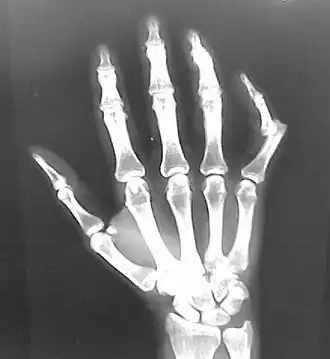

Radiograph of right fifth finger dislocation